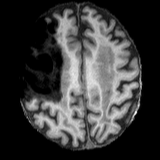

Figure 3: Qualitative comparisons on healthy anatomy reconstruction, between UNA, and the state-of-the-art modality-agnostic T1w synthesis method. Testing images are generated from real healthy subjects encoded with randomly simulated pathology profiles. Pathology regions are circled in red.

Tab. 1 reports the quantitative comparison results between UNA and the state-of-the-art modality-agnostic synthesis models. UNA yields the best performance across all metrics, modalities, and regions of interest – including the full brain, healthy anatomy, and pathological regions. Remarkably, UNA outperforms competing models by a large margin in anatomy reconstruction within diseased tissue. Visualization results for each test modality are provided in Fig. 3. UNA demonstrates consistent performance across modality and resolution. Notably, other models either fail to capture any anatomy (SynthSR [26]) or generate unrealistic patterns around the pathology (Brain-ID [38] and PEPSI [39]) when given a noisy CT scan (4thth{}^{\text{th}}start_FLOATSUPERSCRIPT th end_FLOATSUPERSCRIPT row in Fig. 3), whereas UNA successfully reconstructs plausible healthy anatomy.